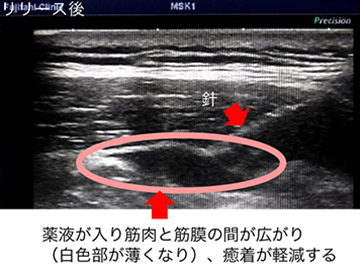

筋膜リリースとは(保険適応外)

Fascia(ファシア)と呼ばれる組織を包む膜の表面に出現する発痛源を注射などで治療する方法を、Fasciaリリース(筋膜リリース)と呼びます。 筋肉を包むFasciaには多くの知覚神経が存在しており、肩こりや慢性腰痛の患者様の筋外膜間には多くの疼痛物質の存在やヒアルロン酸の粘度の上昇が報告されています。 超音波をあてながらこのFasciaと筋肉の間に薬液を注入しリリース(開放)することで、局所補液効果による鎮痛効果(疼痛物質の洗い流し)と、 Fascia同士の摩擦(ストレス)の改善から組織の滑走性や可動性、伸張性の向上が得られると考えられています。副作用の心配はほとんどなく、治療直後からの鎮痛・徐痛が期待されます。

筋膜リリースの画像 筋膜リリースの画像 筋膜リリースの画像